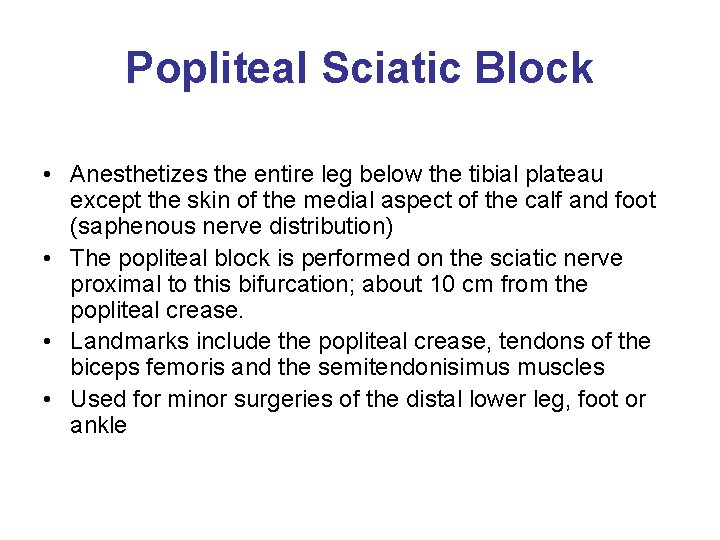

Popliteal Sciatic Block • Anesthetizes the entire leg below the tibial plateau except the skin of the medial aspect of the calf and foot (saphenous nerve distribution) • The popliteal block is performed on the sciatic nerve proximal to this bifurcation; about 10 cm from the popliteal crease. • Landmarks include the popliteal crease, tendons of the biceps femoris and the semitendonisimus muscles • Used for minor surgeries of the distal lower leg, foot or ankle